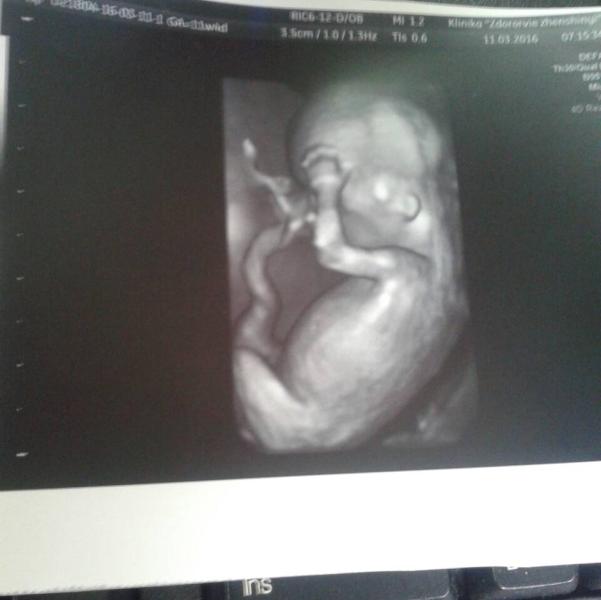

Итак, девочки была я сегодня на первом скрининге в Здоровье Женщины у Курило. Как я ждала этого дня!С мужем увидели малыша, но честно говоря, я думала будет лучше видно. От хваленой Курило что-то я не в восторге, на экране были все-время были какие-то пятна и она их называла частями тела)Самое главное рассказала, что все конечности на месте и органы сформированы и сердечко красивое.Но все-таки напугала меня, ТВП у нас 2,8-3,0 мм. Но при этом малыша она не рассмотрела в профиль, и кашляли и тыка...